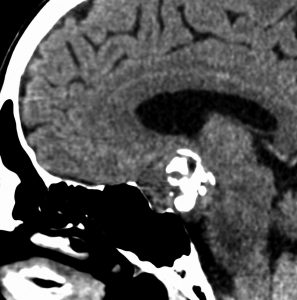

思春期の女の子にできた小脳腫瘍です。とても大きく見えますがほとんどが水たまり(のう胞といいます)。第4脳室が腫瘍で圧迫されて閉塞性水頭症になりました。のう胞の中に出血がありますが毛様細胞性星細胞腫では腫瘍内出血をしばしば見ます。右の写真で脳室が大きくなっています。こんなに大きいのに小脳症状は全くなくて,頭痛と嘔吐が症状でした。

赤で塗ったところだけが毛様細胞性星細胞腫です。これを取れば治ります。簡単な手術ですし後遺症も残りません。

手術後のMRIです。水頭症も改善してますから症状も消失しましたし,すぐに退院です o(^o^)o